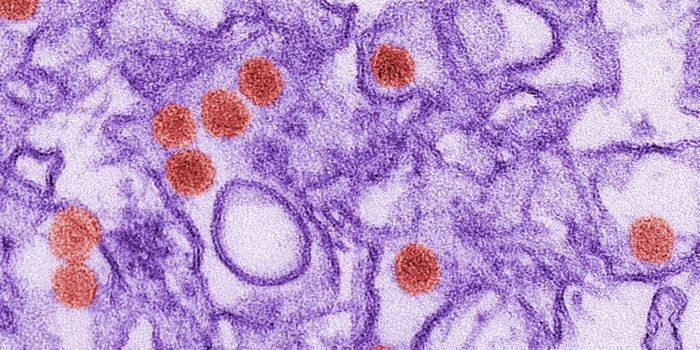

FEB 10, 2019MicrobiologySome viruses, like Zika, can be challenging to study when they suddenly cause outbreaks because they can be very difficu ...